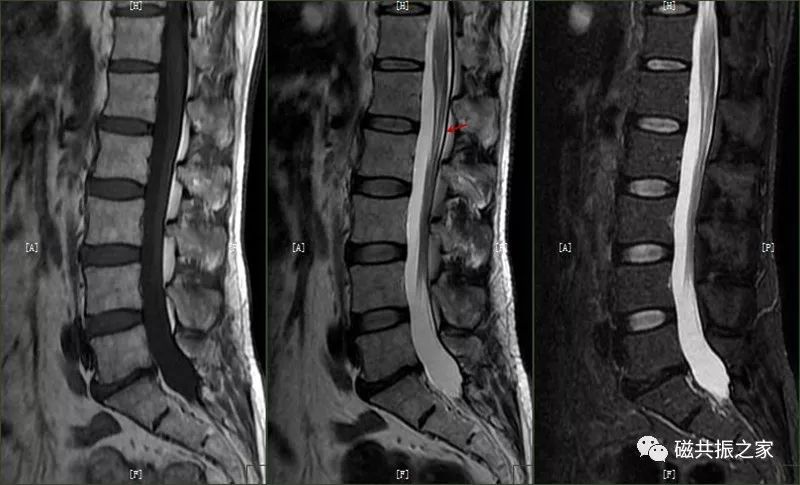

截断伪影常见于 MR 信号强度突然变化的组织界面,如脂肪-肌肉和脊髓-脑脊液界面,可能导致脊髓内出现虚假高信号,易被误解为脊髓空洞或损伤。通过校正编码方向等方法可改善。

化学位移伪影由于人体中水和脂肪内氢质子进动频率差异所致,常出现在水/脂界面,可能被误认为硬脊膜结构。

此外,还有其他容易识别的伪影。骨科金属植入物在高场强时会引起更广泛伪影,表现为低信号强度和脊髓变形。外周信号伪影因线圈单元与扫描范围不匹配产生,有多种表现形式。拼接伪影在脊柱扫描拼接中,因金属异物、参数不一致等因素,导致上下两段对比度不一致。同时,阅片时还需注意不要忽略正常解剖结构,如椎基静脉孔和神经血管脂肪簇等。